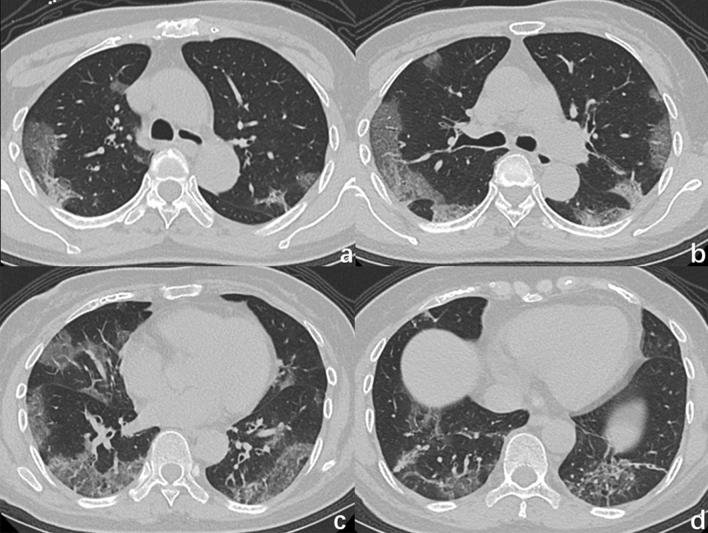

Coronavirus disease 2019 (COVID-19) has spread in more than 100 countries and regions around the world, raising grave global concerns. COVID-19 has a similar pattern of infection, clinical symptoms, and chest imaging findings to influenza pneumonia. In this retrospective study, we analysed clinical and chest CT data of 24 patients with COVID-19 and 79 patients with influenza pneumonia. Univariate analysis demonstrated that the temperature, systolic pressure, cough and sputum production could distinguish COVID-19 from influenza pneumonia. The diagnostic sensitivity and specificity for the clinical features are 0.783 and 0.747, and the AUC value is 0.819. Univariate analysis demonstrates that nine CT features, central-peripheral distribution, superior-inferior distribution, anterior-posterior distribution, patches of GGO, GGO nodule, vascular enlargement in GGO, air bronchogram, bronchiectasis within focus, interlobular septal thickening, could distinguish COVID-19 from influenza pneumonia. The diagnostic sensitivity and specificity for the CT features are 0.750 and 0.962, and the AUC value is 0.927. Finally, a multivariate logistic regression model combined the variables from the clinical variables and CT features models was made. The combined model contained six features: systolic blood pressure, sputum production, vascular enlargement in the GGO, GGO nodule, central-peripheral distribution and bronchiectasis within focus. The diagnostic sensitivity and specificity for the combined features are 0.87 and 0.96, and the AUC value is 0.961. In conclusion, some CT features or clinical variables can differentiate COVID-19 from influenza pneumonia. Moreover, CT features combined with clinical variables had higher diagnostic performance.

2019冠状病毒病(COVID-19)已在全球100多个国家和地区传播,引起了全球的严重关注。COVID-19在感染模式、临床症状和胸部影像学表现方面与流感肺炎相似。在这项回顾性研究中,我们分析了24例COVID-19患者和79例流感肺炎患者的临床及胸部CT数据。单因素分析表明,体温、收缩压、咳嗽和咳痰情况可将COVID-19与流感肺炎区分开来。临床特征的诊断敏感性和特异性分别为0.783和0.747,AUC值为0.819。单因素分析表明,9个CT特征,即中央-外周分布、上下分布、前后分布、磨玻璃影(GGO)斑片、GGO结节、GGO内血管增粗、空气支气管征、病灶内支气管扩张、小叶间隔增厚,可将COVID-19与流感肺炎区分开来。CT特征的诊断敏感性和特异性分别为0.750和0.962,AUC值为0.927。最后,构建了一个多因素逻辑回归模型,该模型结合了临床变量模型和CT特征模型中的变量。联合模型包含6个特征:收缩压、咳痰、GGO内血管增粗、GGO结节、中央-外周分布和病灶内支气管扩张。联合特征的诊断敏感性和特异性分别为0.87和0.96,AUC值为0.961。总之,一些CT特征或临床变量可将COVID-19与流感肺炎区分开来。此外,CT特征与临床变量相结合具有更高的诊断效能。